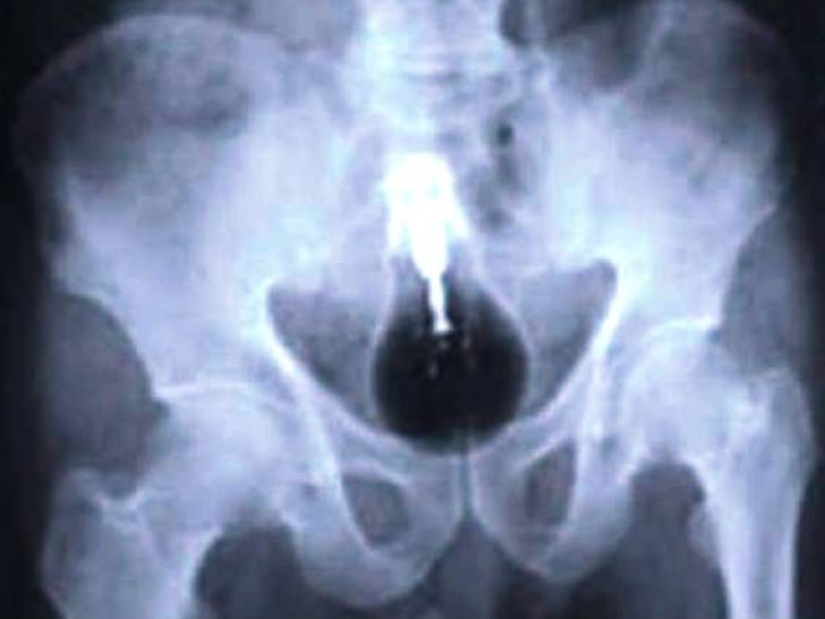

And prisoners also swallow cell phones.